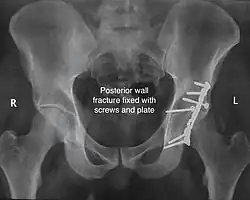

Posterior wall fracture fixed with screws and plate -

Posterior column and wall fixed using screws and plates